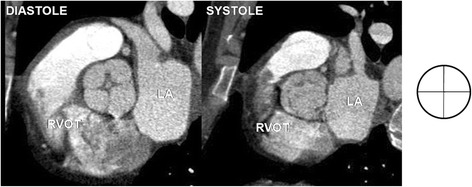

Fig. 5.

Quadricuspid aortic valve - four leaflets, four commissures. RVOT – right ventricular outflow tract, LA – left atrium